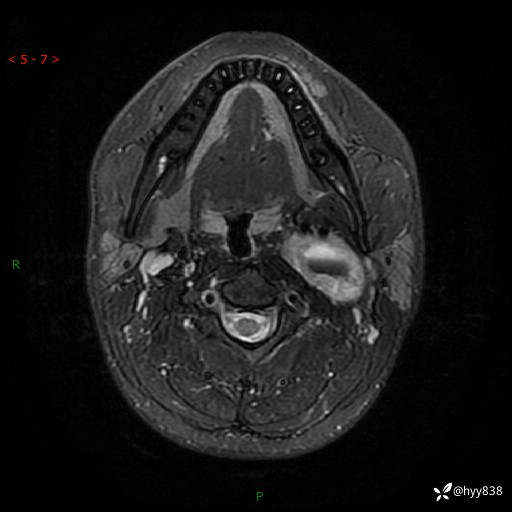

年轻小伙,发现左侧颈部肿物3年余,逐渐增大---结果公布~

现病史:患者约3年前因感冒发现左侧颈部长一肿物,约半个鸡蛋大小,无明显疼痛及其他不适,一直未行特殊处理。3个月前发现左侧颈部肿物变大,随后至当地市第二人民医院耳鼻喉科行左侧颈部彩超示:左侧颈部囊实混合性包块;喉部MPR示:左侧胸锁乳突肌内前方占位,累及左侧喉旁间隙,建议增强扫描。建议手术治疗。患者考虑。随后至我院肿瘤科就诊,行细胞学穿刺示:考虑血管源性肿瘤可能,建议进一步检查。建议至我院口腔科就诊,行颌面部MRI示:左侧颌下腺后方团状异常信号灶,建议增强。建议手术治疗。为求进一步治疗,门诊以“左侧颈部肿物”收入院。 起病以来,患者神志清、精神良好,饮食睡眠良好,大小便正常,体重未见明显变化。

颈部MRI平扫+增强